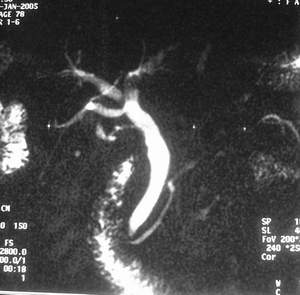

患者,男,57岁,梗阻性黄疸10余天。

这个病例胰头无明显增大,胆总管扩张明显而肝内胆管扩张更不明显,病程较短,

注意到十二指肠乳头明显突出,但尚光滑。分析以下可能性:

1、十二指肠乳头本身的病变,如乳头炎症;

2、急性乳头水肿,胆总管下端结石排石后乳头水肿;

3、壶腹部胆总管下端肿瘤累及十二指肠乳头。

十二指肠乳头粘膜慢性非特异性炎症